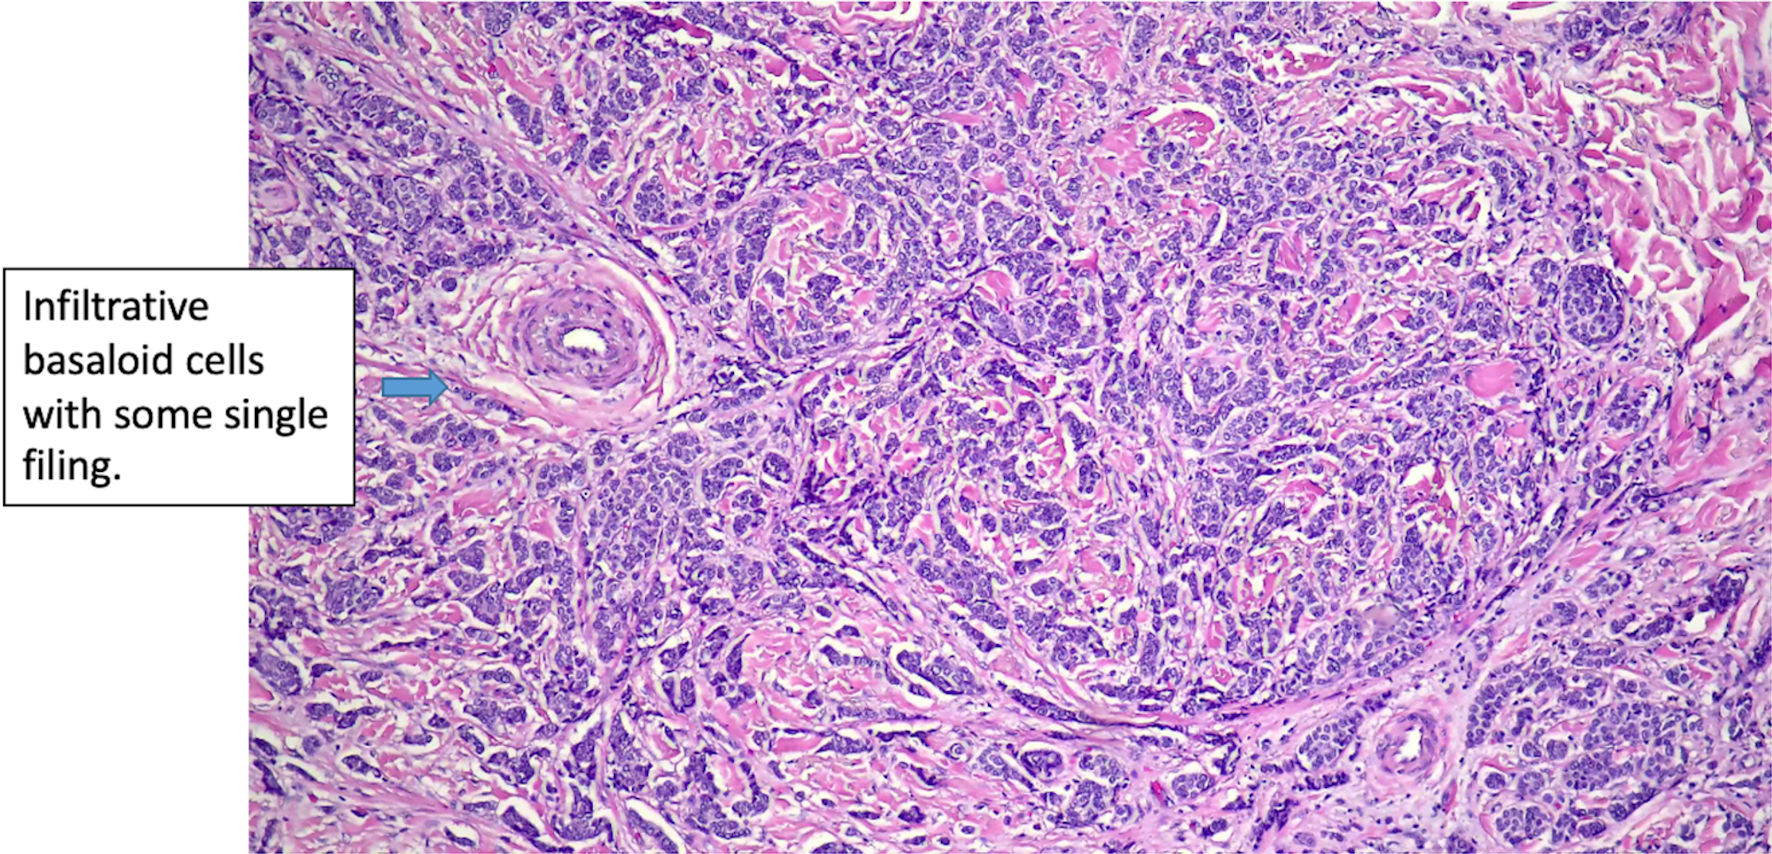

Figure 5. Histologic features of eccrine cell carcinoma at excision. The carcinoma is infiltrative, largely involving the dermis (original magnification × 50).

Click for large image

The patient is a 66-year-old female who presented to our facility in 2024 with a recurrent left lower lip lesion characterized by throbbing pain and numbness. The lesion was initially found in 2017 and later recurred twice in 2020 and 2023, which was managed at another facility. The first surgery was done in 2017 with R0 resection. Pathology report of the recurrent lesion revealed invasive carcinoma, likely ductal carcinoma of the breast with neuroendocrine differentiation. Immunohistochemical stains were positive for CK7, GCDFP-15, mammaglobin, ER (99% strong), PR (99% strong), synaptophysin, and chromogranin, while negative for S100 and p63. E-cadherin showed a strong membranous pattern, suggestive of a ductal phenotype (Figs. 1-7). These findings indicated a primary ductal carcinoma of the breast. However, further investigation revealed no evidence of primary breast cancer. The recurrence of the lesion in 2020 led to another R0 resection, revealing a poorly differentiated carcinoma with potential neuroendocrine and sebaceous differentiation. The patient subsequently developed pain and contractures in the excision area, which prompted her to consult plastic surgery services in 2023, leading to lip reconstruction and another biopsy. This procedure resulted in an R2 resection, with the finding of poorly differentiated adenocarcinoma with extensive perineural invasion evident at the margins. Accessory breast tissue was carefully examined, but no trace of it was found in any of the slides. The pathology slides were originally obtained from the outside facility and reviewed by a dermatopathologist and breast-specialized pathologist. In their interpretation, in the absence of breast lesions, a diagnosis of eccrine carcinoma was considered more appropriate - a known diagnostic pitfall.